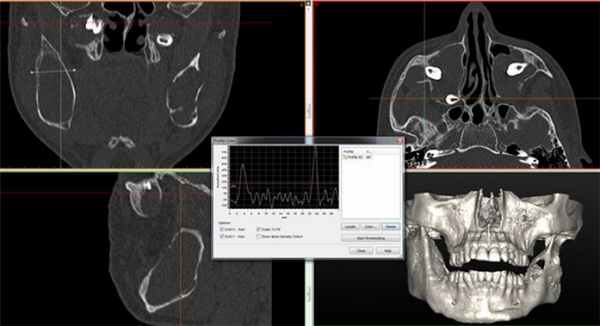

Клинический случай №5

Пациент муж., 17 лет. КТ-исследование подтверждает наличие новообразований (Рис. 6,7).

Рис. 6. Ортопантомограмма пациента с одонтогенными кератокистами.

КТ свидетельствует о наличии множественных одонтогенных кератокист. Определяются множественные овальные, зубосодержащие полости, с четкими ровными справа и полицикличными контурами слева, однородной рентгенпрозрачности. В теле и ветвях нижней челюсти образование распространяется вдоль кости от премоляров справа и моляров слева и до вершин мыщелковых отростков. Костные структуры незначительно увеличены в размерах за счет вздутия, кортикальные пластины истончены. Дивергенция корней зубов № 43, 44. Объемные зубосодержащие образования верхней челюсти вросли в верхнечелюстные синусы, занимая практически весь объем, а справа — распространилось в подвисочную ямку.

Рис. 7. КТ исследование свидетельствует о наличии множественных одонтогенных кератокист.